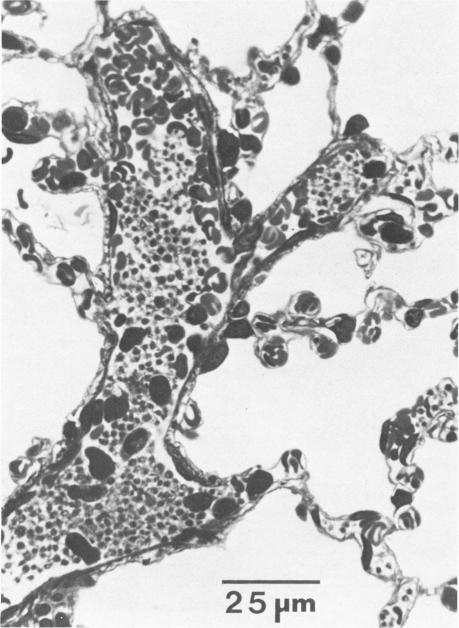

Acetyl glyceryl ether phosphorylcholine (AGEPC; 1-O-hexadecyl-2-acetyl-sn-glyceryl-3-phosphorylcholine) was infused intravenously into rabbits (0.5 micrograms/kg); subsequently, temporal pulmonary alterations were assessed histologically. Within 30 seconds after AGEPC infusion, widespread platelet and neutrophil aggregates were distributed throughout the pulmonary microvasculature. Concomitantly, small muscular arteries and bronchioles throughout the lungs were contracted. Five minutes after AGEPC infusion, intravascular pulmonary platelet aggregates were less frequent and smaller than those observed at 30 seconds after infusion; however, AGEPC-induced pulmonary neutrophil sequestration persisted. Moreover, at this time, large mononucleated cells and damaged endothelial cells were prevalent throughout the pulmonary microvasculature. Sixty minutes after infusion, neither platelet aggregates nor arterial or bronchiolar constriction was observed. However, in most animals, neutrophils and large mononucleated cells were still abundant, and focal endothelial cell alterations persisted. In addition, discrete areas of interstitial hemorrhage around small and medium-sized arteries were present. These studies suggest that the intravascular release of AGEPC could initiate significant pulmonary injury and therefore could be an important etiologic factor in the development of inflammatory lung diseases.

将乙酰甘油醚磷酸胆碱(AGEPC;1-O-十六烷基-2-乙酰基-sn-甘油-3-磷酸胆碱)以0.5微克/千克的剂量静脉注射到兔子体内;随后,通过组织学评估肺部随时间的变化。在注入AGEPC后30秒内,广泛的血小板和中性粒细胞聚集体分布在整个肺微血管系统中。与此同时,肺部各处的小肌性动脉和细支气管收缩。注入AGEPC后5分钟,血管内肺血小板聚集体比注入后30秒时更不频繁且更小;然而,AGEPC诱导的肺中性粒细胞滞留持续存在。此外,此时,大单核细胞和受损内皮细胞在整个肺微血管系统中普遍存在。注入后60分钟,未观察到血小板聚集体或动脉或细支气管收缩。然而,在大多数动物中,中性粒细胞和大单核细胞仍然大量存在,局部内皮细胞改变持续存在。此外,在中小动脉周围存在离散的间质出血区域。这些研究表明,AGEPC的血管内释放可引发严重的肺损伤,因此可能是炎症性肺病发展的重要病因。